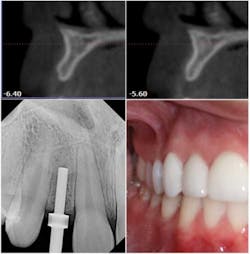

The ability to access the anatomical structures before starting the implant makes 3-D technology a good investment. The patient's chair time is greatly reduced with 3-D as a diagnostic tool. Without the CBCT scan, whether the patient needs one implant or a full arch of them, bone volume still has to be determined. With a CBCT scan, I will find out the dimension of the bone without taking a blade to the patient.

Patients appreciate that. Even with a 2-D panoramic, I would still have to anesthetize the patient and perform some bone sounding with calipers to find the buccal-lingual width of the bone. The scan illustrates precisely what is under the tissue, and the patient is put through less discomfort for a shorter time.

Digital technology saves an astronomical amount of surgical time and improves the success of implants. When I can take digital (DEXIS®) PAs during surgery, I am sure that I am navigating between existing teeth and maintaining distance and parallelism. It is invaluable to me to have that information instantaneously. It shortens the time I have to wait with an open surgical site. Again, this is something patients appreciate.